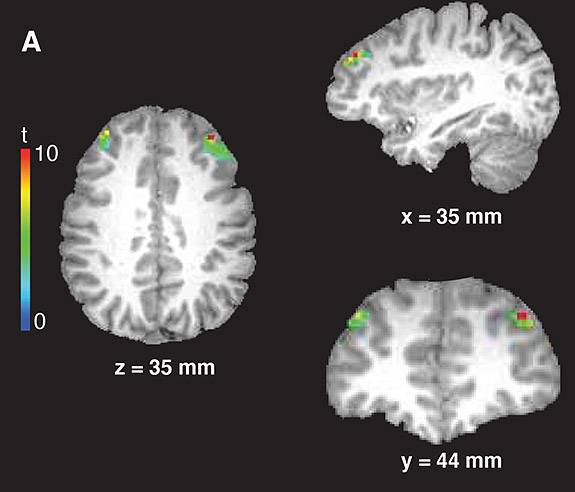

With the fMRI, the researchers detected activity in the right prefrontal cortex during tasks that required the participants to remember whether they saw an A or a B before pressing the correct button, but not during tasks where the participant only had to press the button when prompted by an X.

Finally, the researchers explored their theory that dopamine — a naturally occurring chemical involved in motivation and reward among other brain functions — tags new information entering the prefrontal cortex as important for updating working memory and goals. Cohen and his team imaged a brain region called the midbrain, which contains clusters of nerve cells called dopaminergic nuclei that are the source of most of the dopamine signals in the brain. Using high-resolution fMRI, the researchers probed the activity of these dopamine-releasing cells in the brains of volunteers engaged in the game described above. The researchers found that the brain activity in these areas correlated both with the activity in the right prefrontal cortex and with the ability of the volunteers to press the correct buttons.